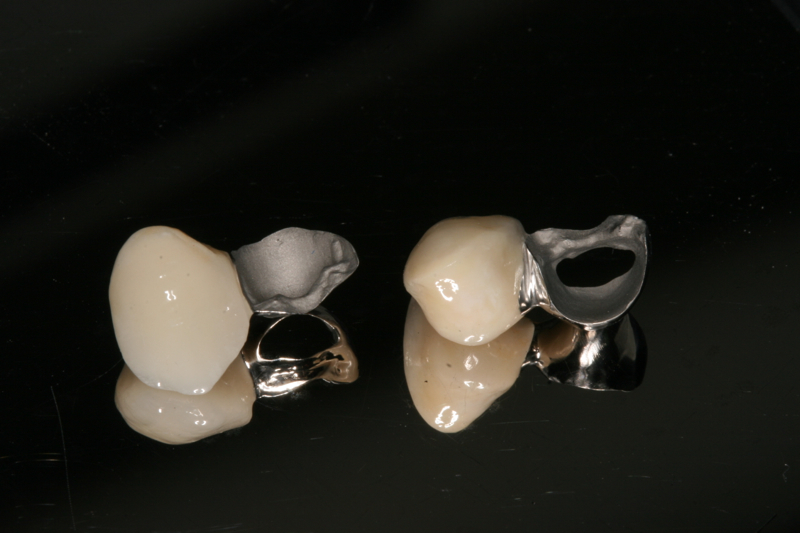

Saving your own teeth can involve complex procedures. Sometimes it may not be possible or practical to be able to save a tooth and alternatives may need to be considered.

The management of complex dental rehabilitation requires careful planning and consideration of all the associated problems. When managing complex cases, it is usually necessary for other specialist clinicians to be involved in restoring the mouth to normal. This provides the best chance to correct any underlying problems that caused tooth destruction, and may reduce the amount of prosthetic work you require. We frequently work alongside other specialists such as Orthodontists, Periodontists, Endodontists and Maxillo-facial Surgeons to develop solutions to your individual problems.

Dr Parzham has an interest in the management of complex multi-disciplinary rehabilitations of severely broken down teeth.